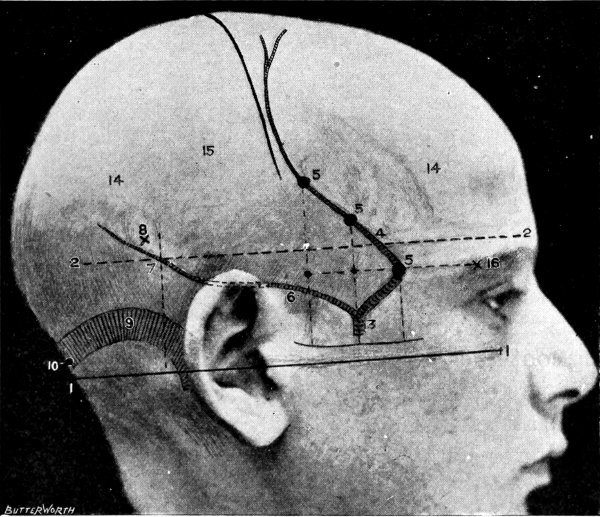

Fig. 1. Cranio-cerebral Topography. 1, The nasion; 2, The inion; 3, The mid-point between nasion and inion; 4, The Rolandic fissure; 5, The superior temporal crest; 6, The inferior temporal crest; 7, The Sylvian point; 8, The anterior horizontal limb of the Sylvian fissure; 9, The vertical limb of the Sylvian fissure; 10, The posterior horizontal limb of the Sylvian fissure; 11, The parietal prominence; 12, The malar tubercle; 13, The lambda; 14, The first temporo-sphenoidal sulcus; 15, The external parieto-occipital sulcus; 16, The lateral sinus; 17, 17, 17, The level of the base of the cerebrum; 18, The external auditory meatus; 19, 19, Reid’s base-line. (Reproduced, by the permission of Mr. H. K. Lewis, from the author’s work on ‘Landmarks and Surface-markings’.)

Fig. 2. Cranio-cerebral Topography. 1, 1, Reid’s base-line; 2, 2, A line parallel to the above at the level of the supra-orbital margin; 3, The middle meningeal artery; 4, The anterior branch; 5, 5, 5, The three sites for trephining; 6, The posterior branch; 7, The site for trephining; 8, The point for trephining to reach the descending horn of the lateral ventricle; 9, The lateral sinus; 10, The inion; 11, The mastoid process; 12, Macewen’s suprameatal triangle; 12a, The mastoid antrum; 12b, The facial nerve; 13, The suprameatal and supramastoid crests; 14, 14, The temporal crest; 15, The temporal fossa; 16, The external angular frontal process; 17, The tendo-oculi attachment; 18, The lachrymal groove. (Reproduced, by the permission of Mr. H. K. Lewis, from the author’s work on ‘Landmarks and Surface-markings’.)

The surgeon who is called upon to carry out operations on the skull and brain must possess an accurate knowledge of the anatomy of the parts involved. Added to this, he must have at his command some simple method of depicting on the surface of the skull the more important structures.

The more complicated systems of cranio-cerebral topography are of little practical value to the surgeon. Simplicity is essential, and the following outline will be found to furnish an adequate practical guide.

Firstly, the skull can be divided into two lateral halves by the surface-marking of the superior longitudinal venous sinus.

This sinus originates at the crista galli and, passing backwards along the attached margin of the falx cerebri, terminates at the internal occipital protuberance. It may be represented by a line drawn from the base of the nose (the nasion), over the vertex of the skull, to the external occipital protuberance (the inion)—this line corresponding in its course to the occasionally persistent metopic suture between the two halves of the frontal bone, to the sagittal suture between the parietal bones, and to the middle line of the upper or tabular portion of the occipital bone.

Secondly, each lateral half of the skull can be subdivided into supra- and infratentorial regions by a line which marks the external attachment of the tentorium cerebelli; in other words, by the line of the lateral sinus.

This sinus is represented by a line presenting a slight upward convexity, which is drawn from the external occipital protuberance to the upper and posterior part of the mastoid process of the temporal bone.

These landmarks having been determined, the following structures may be mapped out on the surface of the skull.

This artery is given off from the internal maxillary; after a short extra-cranial course it enters the skull through the foramen spinosum, and soon divides into two main terminal branches. The site of division corresponds to a point situated just above the centre of the zygoma.

The anterior branch passes at first in a forward and upward direction towards the anterior inferior angle of the parietal bone, and then turns upwards and backwards towards the vertex of the skull. The main ‘danger zone’ in the course of this vessel may be mapped out by taking points which lie respectively 1, 11⁄2, and 2 inches behind the external angular frontal process and an equal distance above the upper border of the zygoma. A line uniting these three points represents that part of the anterior division of the middle meningeal artery which is most liable to injury and which therefore most frequently requires exposure.

The uppermost point may, however, be regarded as the ‘site of election’ for exposure of the artery, as, in trephining over either of the two lower points, difficulty may be experienced in the removal of the disk of bone, since the posterior border of the great wing of the sphenoid tails off on to the anterior inferior angle of the parietal bone in such a manner that to effect a clean removal of the disk is often impossible. Another disadvantage to trephining low down lies in the fact that in about 30 to 40 per cent. of cases the artery occupies, in that situation, a canal in the bone.

The posterior branch passes almost horizontally backwards, parallel to the zygoma and supramastoid crest, towards the posterior inferior angle of the parietal bone. The vessel can readily be exposed[6] by trephining over the point at which a line drawn backwards from the upper border of the orbit, parallel to Reid’s base-line,[1] cuts another line directed vertically upwards from the posterior border of the mastoid process.

Both branches of the middle meningeal artery possess important relations to the cortex cerebri, the anterior branch passing upwards in relation to the precentral or motor area, traversing, from below upwards, the motor speech area (on the left side of the head), the centres for the movements of the face, upper extremity, trunk, and lower extremity. The posterior branch, on the other hand, passes backwards in relation to the temporo-sphenoidal lobe, one of the so-called ‘silent areas’ of the brain. Throughout their course the middle meningeal vessels lie between the dura mater and the bone.

The lower limit of the cerebrum can be mapped out in the following manner: From a point situated about 1⁄2 inch above the nasion a line is drawn outwards which follows the curve of the upper border of the orbit as far as the external angular frontal process, thence curving upwards and backwards to the Sylvian point (see below). The temporo-sphenoidal lobe sweeps forwards to the posterior border of the malar bone, and its lower limit lies practically flush with the upper margin of the zygoma. At and behind the ear the lower limit of the cerebrum corresponds to the suprameatal and supramastoid crests, subsequently following the curve of the lateral sinus from the mastoid process to the external occipital protuberance.

The Sylvian point represents the site of divergence of the three limbs of the Sylvian fissure. It lies 11⁄4 inches behind the malar tubercle and 11⁄2 inches above the upper border of the zygoma. The main posterior horizontal limb passes backwards and upwards to a second point situated 3⁄4 inch below the parietal prominence.

The vertical limb is directed upwards for about 1 inch, whilst the anterior horizontal limb passes forwards for about the same distance.

This, from a surgical point of view,[7] the most important fissure of the brain, is represented as follows: A point is taken in the median antero-posterior line which lies 1⁄2 inch behind the mid-point between nasion and inion, and from this point a line is drawn, for 31⁄2 to 4 inches, towards the mid-point of the zygoma. This line is inclined to the median antero-posterior line at an angle of 671⁄2° (three-quarters of a right angle).

In the representation of these two fissures, two points require to be determined—the malar tubercle and the lambda. Allusion has already been made to the former; the latter is usually readily located as the point of intersection of the sagittal and lambdoid sutures. A line uniting these two points corresponds in its middle third to the temporo-sphenoidal fissure, and in its posterior inch or so to the external parieto-occipital sulcus, a fissure separating the occipital and parietal lobes of the brain.